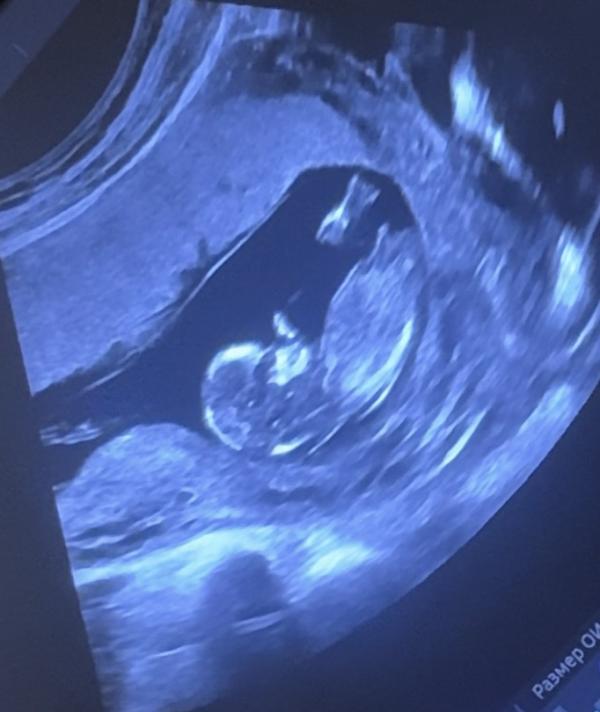

Малыши лежат как в гороскопе знак Рыбы)

По 6 см примерно(на прошлом узи в 11 нед. были по 4,5) один чуть больше другого. Послушали сердцебиение (тх тх тх тх тх тх), все хорошо, все по сроку.